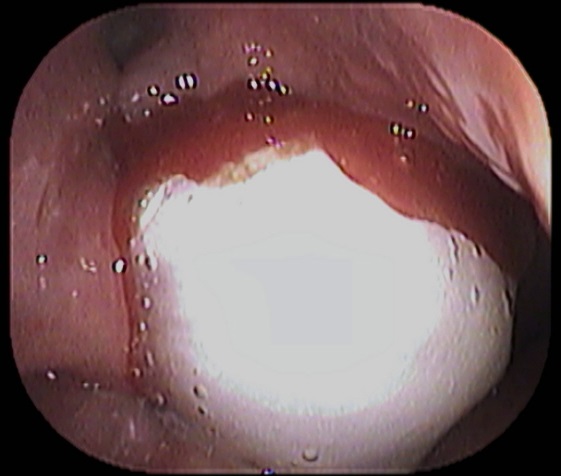

昨日 サバ

を食べてからノドが痛いとのことで当院受診された患者さんがおられました。

まずはノドを診てみます。

無さそうです。

次はファイバーでノドの奥をチェックしてみます ![]()

ありました ![]()

場所はどこかと言いますと

「 舌扁桃(ぜつへんとう) 」と呼ばれる場所です。

刺さっているイメージとしてはこんな感じです↓

そして取れた魚骨は↓

1.5cm大 でした。

魚の骨が気になる方は、耳鼻咽喉科でのチェックをオススメいたします ![]()